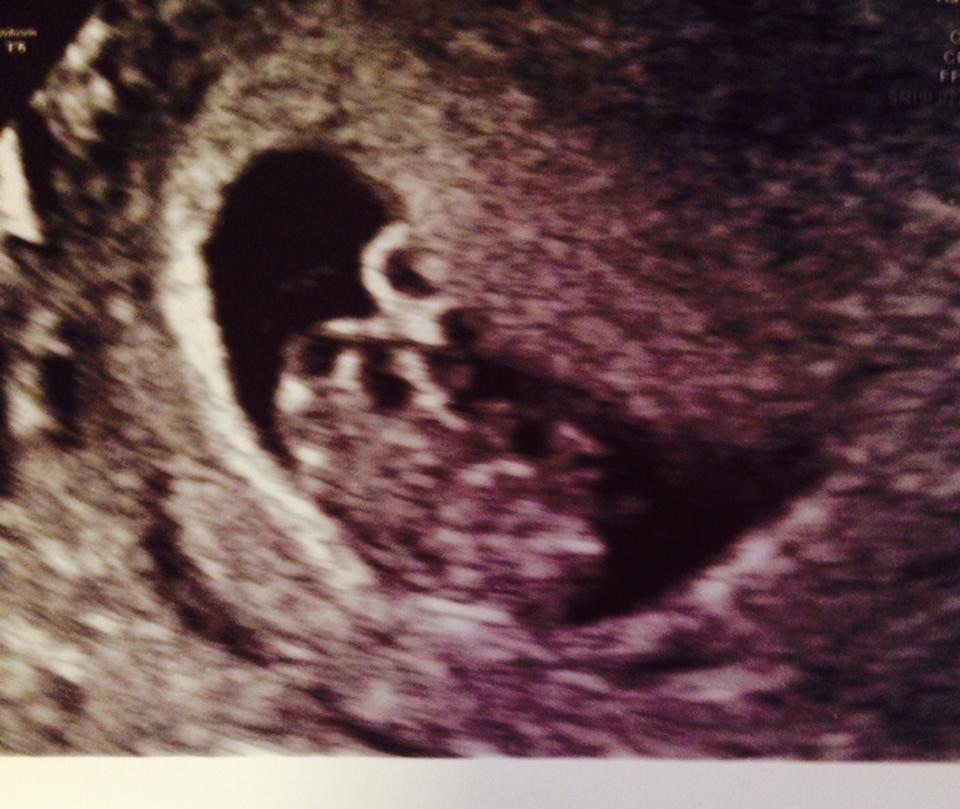

My babies first scan nearly 9 weeks

Attachment 21165